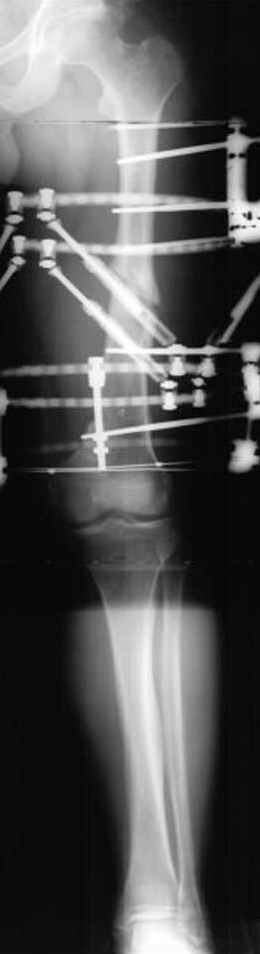

пластическая модель; и коррекция бедра аппаратом Илизарова.

Имею другие снимки тоже, получится как отчет о моей работе.